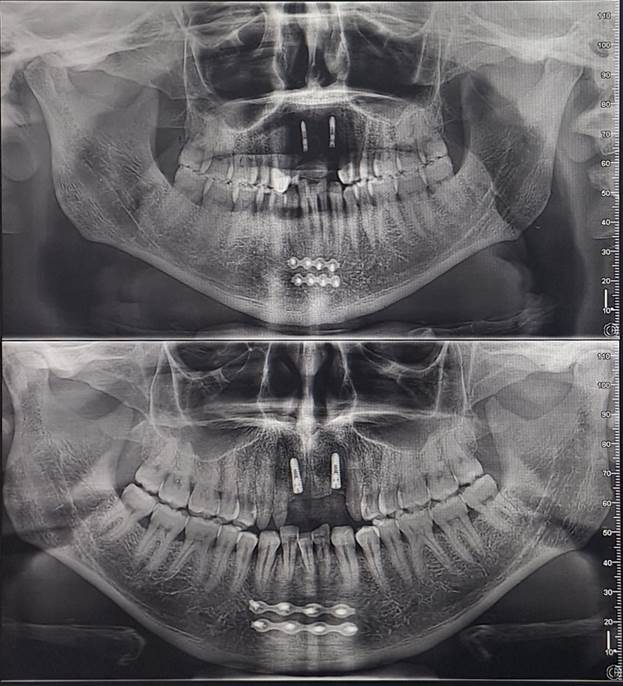

I recently received images of the damage when I got my teeth

repaired and have provided them below.

However, I woke up covered in blood, as was all my bedding.

I went to the mirror and saw the extent of the damage. My lower jaw had split

into two halves, divided straight down the front center. I decided not to